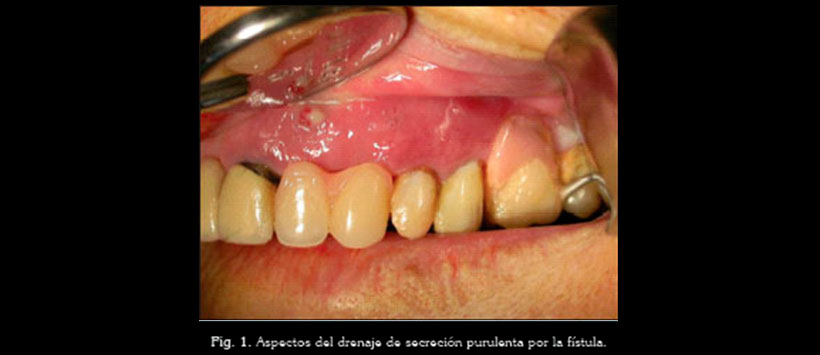

El examen intraoral evidenció la presencia de dos fístulas localizadas en la región de los dientes 2.2-2.3 (ausentes) y 2.4-2.5 (con movilidades). Presencia de reabsorción de la tabla ósea vestibular y drenaje de secreción purulenta por la fístula a través de una compresión en la zona (Figura 1).